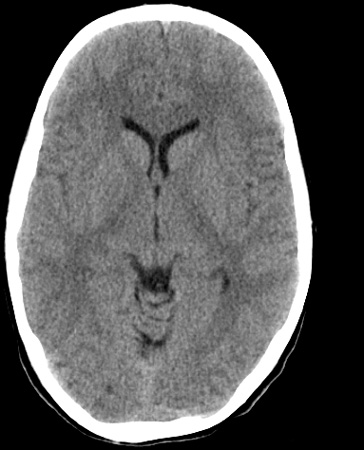

Identify the following structures in the head CT. To view the location of the structure in the image click on the label at the left and an arrow will point to the structure in the image.